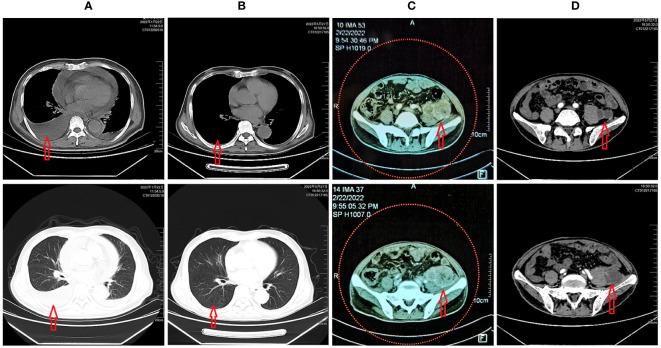

A rare adverse effects of COVID-19 vaccine in a patient with a latent tumor: A case report and literature review.

The 2019 novel coronavirus infection has done significant damage to the world. The effectiveness and safety of the vaccine, the most critical measure to control the epidemic, has attracted attention. In this case, we report the diagnosis and treatment of a rare patient with adverse effects of the COVID-19 vaccine who had G6PD deficiency by genetic tests. We discuss the possible impact of G6PD deficiency on COVID-19 infection and potential vaccine adverse effects. Patients with severe G6PD deficiency should be monitored for vaccine safety. This article may complement a rare mechanism of vaccine side effects and chemotherapy-related side effects.

2019新型冠状病毒感染给世界造成了重大破坏。疫苗作为控制疫情的最关键措施,其有效性和安全性备受关注。在此情况下,我们报告了1例经基因检测确诊为葡萄糖-6-磷酸脱氢酶(G6PD)缺乏症的新型冠状病毒肺炎(COVID-19)疫苗不良反应罕见患者的诊疗情况。我们探讨了G6PD缺乏症对COVID-19感染及潜在疫苗不良反应的可能影响。对于严重G6PD缺乏症患者,应监测疫苗安全性。本文可能补充了一种罕见的疫苗副作用及化疗相关副作用机制。